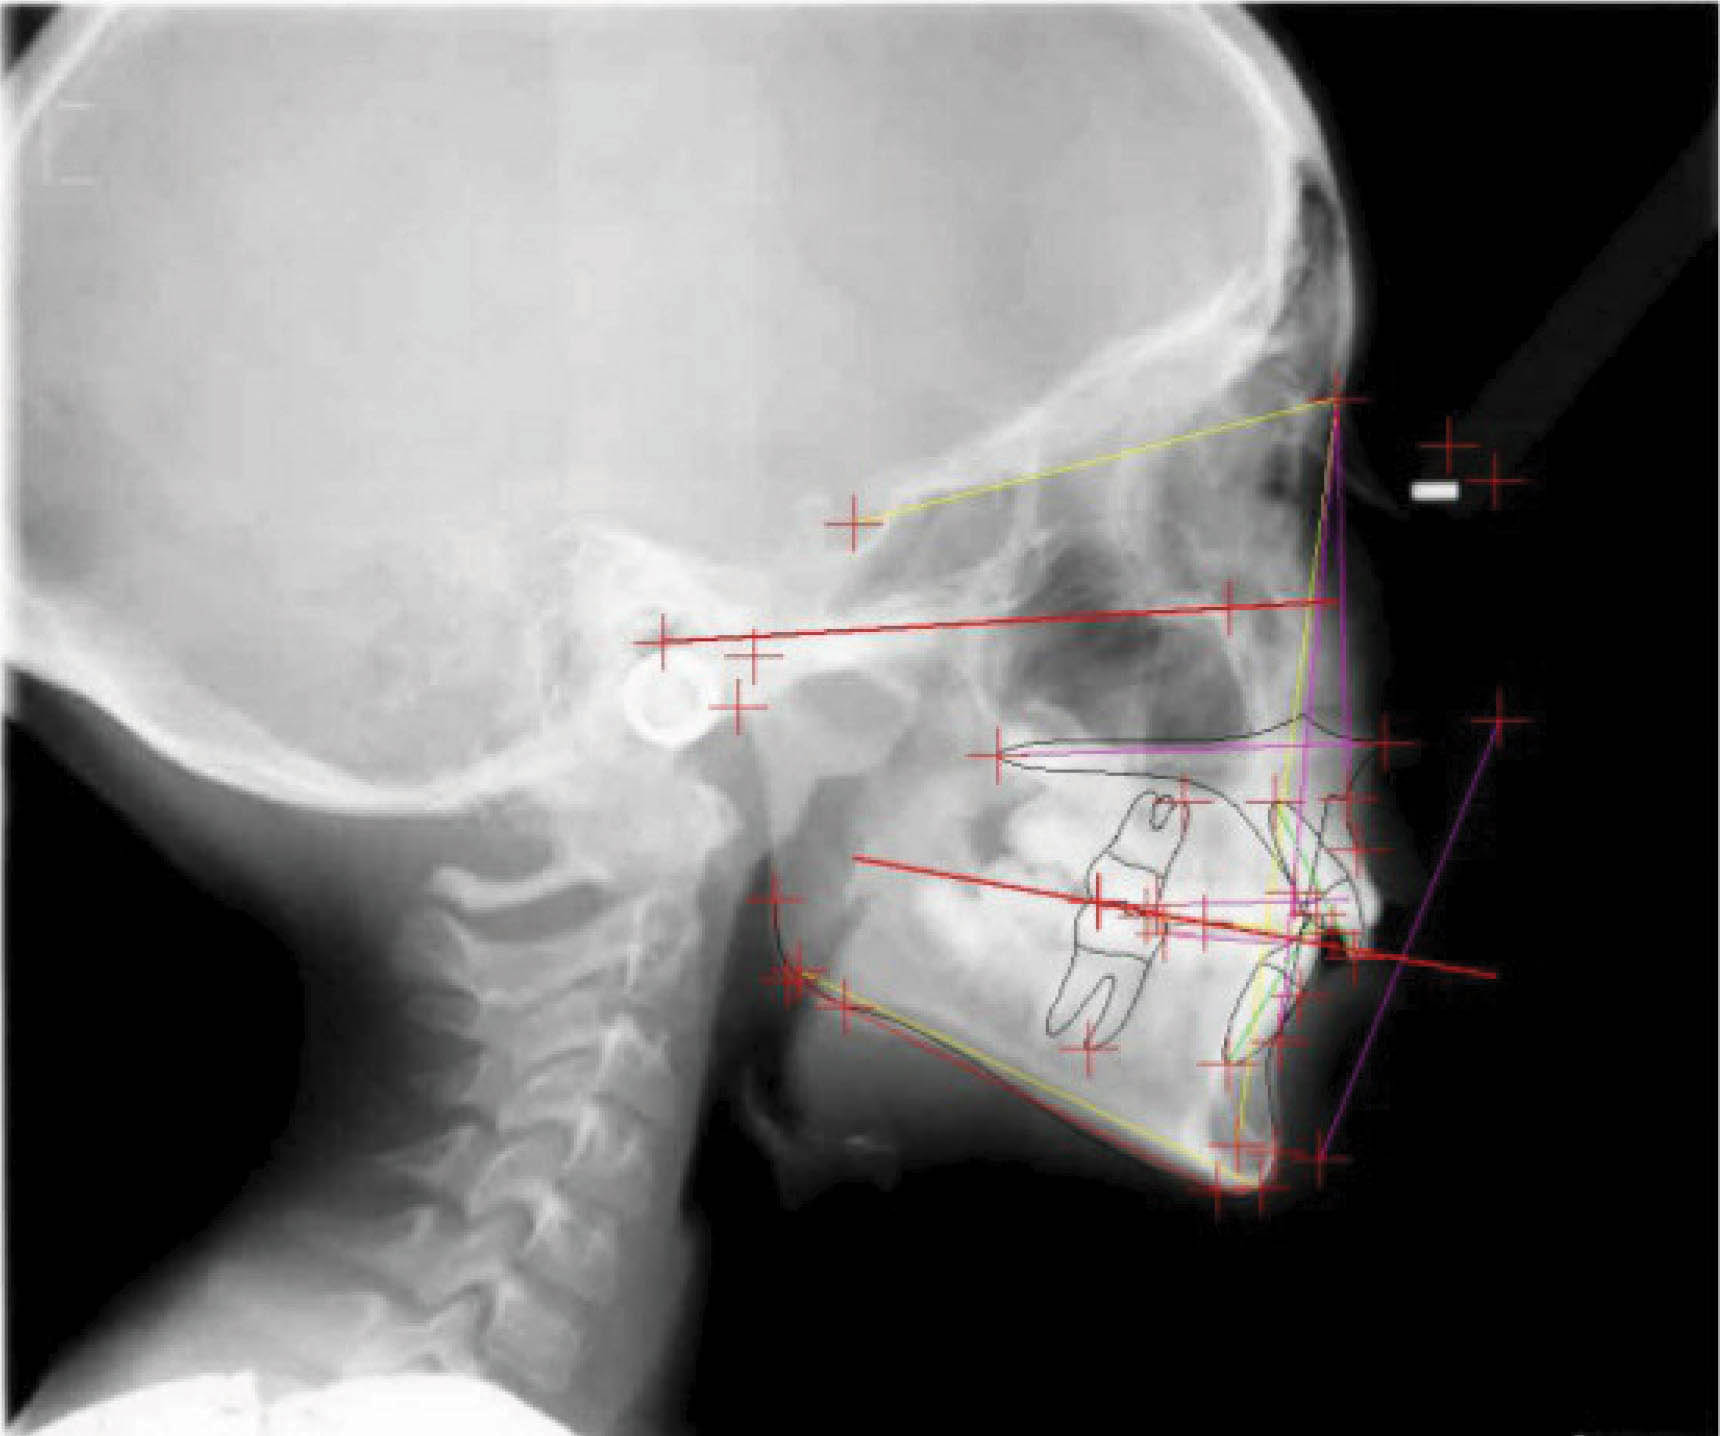

بیمار بعدی یک دختر ۱۶ ساله ClII/1 با اوربایت نرمال و اورجت زیاد است. کرادینگ مختصر دو فک دارد، قوس بالا تنگ، و پروفایل او طبیعی است (شکل 83-۶ الی 85-۶). در این بیمار از الاستیک کلاسII استفاده شده است. الگو اسکلتی طبیعی، رادیوگرافی لترال سفالومتری نشان دهنده دندانهای قدامی پروترود شده بالا با الگو طبیعی اسکلتی میباشد. رادیوگرافی OPG طبیعی است. قسمت بعُد افقی چک لیست را به این نحوه پر کردیم:

شکل 84-6

در انتهای درمان (شکلهای 89-۶ الی 91-۶) اکلوژن کلاسI شده است. دندانها مرتب شدند و اوربایت و اورجت طبیعی و به حداکثر زیبایی دست یافتیم. عکس نهایی OPG طبیعی است. مقایسه عکسهای لترال ابتدا و انتهای درمان نشاندهنده تغییر قابل ملاحظه موقعیت انسیزورهای بالا است که منجر به اصلاح اورجت گردیده است. لبخند او عالی گردید.